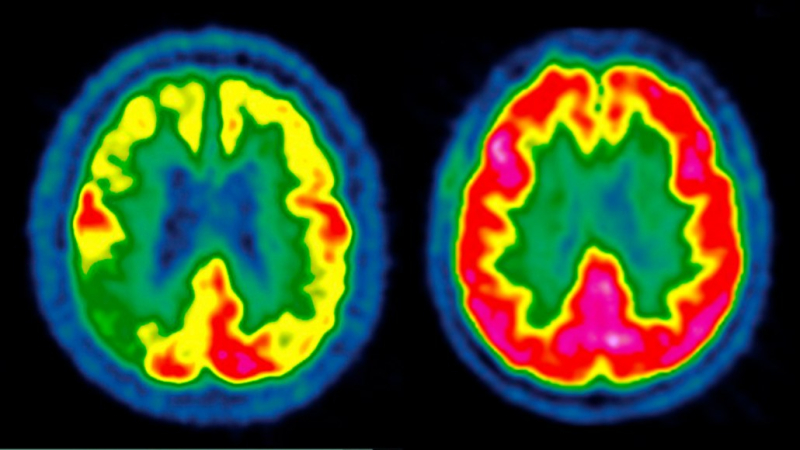

Ранее ученые показали, что активность мозга человека с болезнью Альцгеймера (слева) может быть снижена от низкой (синий) до высокой (красный) по сравнению со здоровым человеком (справа). В ходе двух новых клинических испытаний ученые надеялись замедлить прогрессирование заболевания, назначая пациентам препарат GLP-1, но лечение оказалось безуспешным.

Два крупнейших клинических испытания такого рода развеяли надежды на то, что “чудо-лекарство” от диабета и снижения веса может также оказать магическое воздействие на болезнь Альцгеймера.

Ежедневная доза семаглутида для приема внутрь не замедлила прогрессирование нейродегенеративного заболевания, сообщили авторы исследования 3 декабря на конференции «Клинические испытания болезни Альцгеймера» в Сан-Диего.